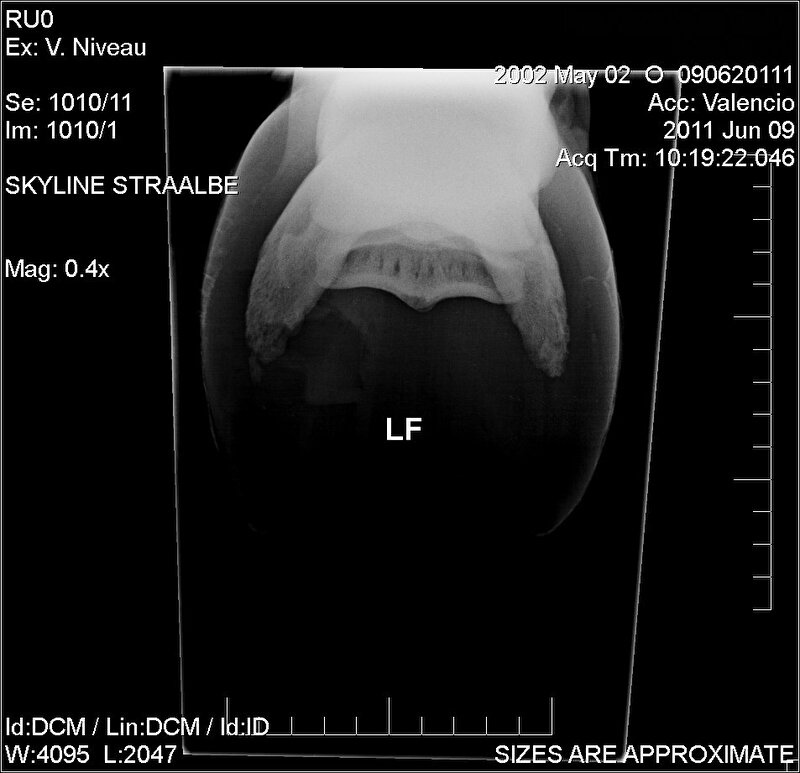

Is er ook een foto van onder af de hoef genomen? Ik heb een paard gehad met HKO, en de "standaard" röntgenfoto zag je het niet op.

Tot dat je een foto zag van de onderkant af.

Dit is de foto:

Afbeelding

Er is alleen een foto van voor- en van de zijkant gemaakt.

Oke dan kan je nog een foto van onder af laten maken.. Of MRI, dan weet je het direct maar dat is prijzig.